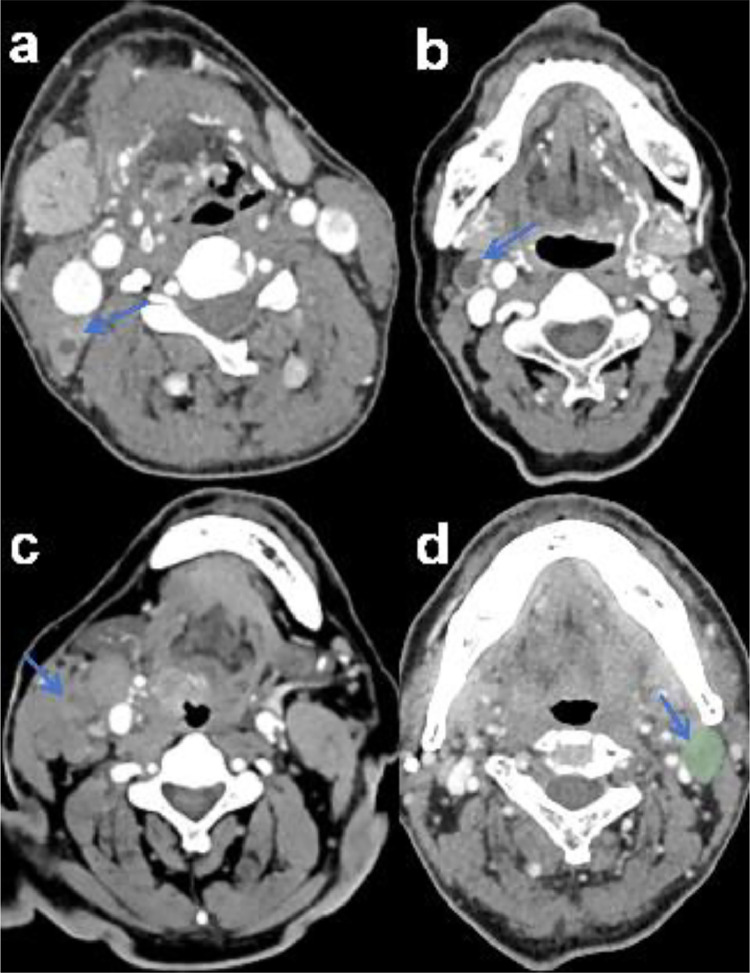

Methods and materials: Data from patients who visited the authors' hospital between January 2018 and February 2023 were retrospectively reviewed. Eighty-six patients with OPSCC contributed 116 LNs, which were randomly divided into training and test sets. Radiologists derived CT signs characteristic of each LN by visually reviewing CT scan images. The radiomics features of LNs were extracted using "3Dslicer" (https://www.slicer.org), and the least absolute shrinkage and selection operator method was used to reduce the dimensions and establish radiomics tags. A CT scan-based radiomic nomogram was constructed and validated. The performance levels of the radiomics nomogram, radiomics signature, and CT-sign model were evaluated according to the area under the receiver operating characteristic curve (AUC) values.

Results: CT signs (central necrosis, extensive necrosis, and LN accumulation) exhibited significant differences between the LN-negative and LN-positive groups. For each CT scan, 851 3-dimensional features were extracted from the cervical LN region. Eight of the most pertinent radiomic features were selected using dimensionality reduction to create radiomic tags. The radiomics nomogram incorporating the CT signs and radiomics signature demonstrated favorable predictive value for diagnosing LNM in patients with OPSCC, with the area under the receiver operating characteristic curve values of 0.983 and 0.919 for the training and test sets, respectively.